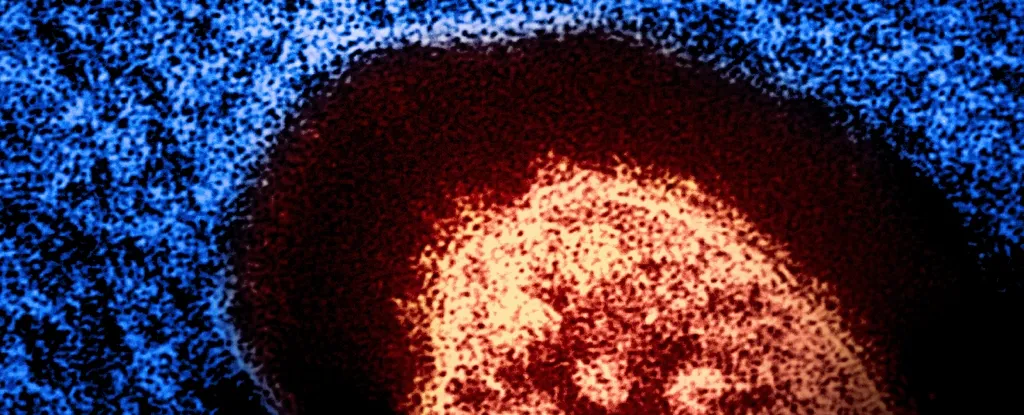

Сліпота, пневмонія, важка діарея та навіть смерть – інфекції, спричинені вірусом кірки, особливо небезпечні для дітей і можуть призвести до руйнівних наслідків. На щастя, сучасна медицина має надійний захист: вакцини проти кірки, які, за оцінками, запобігли більше ніж 60 мільйонам смертей у період з 2000 по 2023 рік.